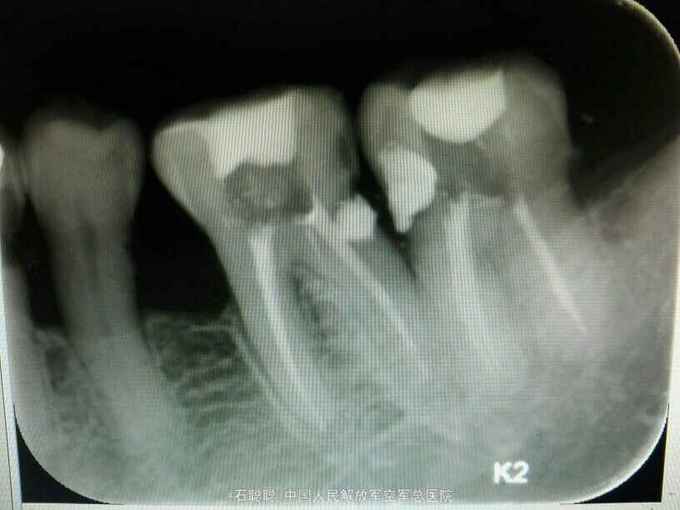

检查:36、37合面白色暂封物完整在位,叩痛-,无明显松动,36、37之间牙龈退缩,见食物嵌塞 根尖片:36、37根管内高密度充填影像,恰填,牙周膜宽度、根尖未见明显异常,36远中牙颈部、37近中牙颈部见低密度透射影像,牙槽骨轻度吸收至釉牙骨质界下方约2mm

诊断:36、37牙体缺损 治疗计划:36远中、37近中植入纤维桩 烤瓷联冠修复 处置:36、37去除氧化锌暂封,见36远中偏舌侧壁缺损、断面位于龈上1mm,37近中偏舌侧壁缺损、断面平齐龈缘,其余轴壁厚度高度完整 36远中舌侧根管预备桩道,度13mm,1#P钻,37近中舌侧预备桩道,长度14mm,1号P钻,各植入黄玻璃纤维桩一枚,堆树脂核,备牙,取模,比色:A3.5,寄送加工厂,制作临时冠,调合,粘接 一周后复诊: 检查:36、37临时冠完整在位,叩痛-,牙龈未见异常 处置:36、37去除临时冠,清楚粘结剂,试戴36、37银钯合金烤瓷联冠,调合,磨光,粘接